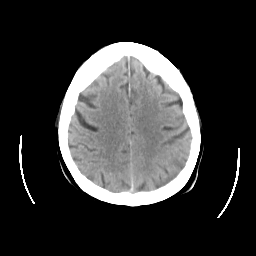

CT Study #2 -- Slice #21